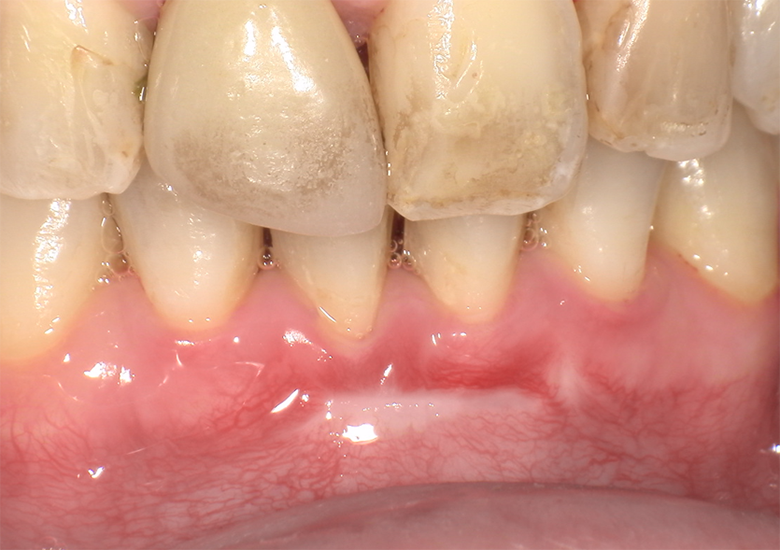

治療前 ![]() |

矯正治療後、下顎前歯の隙間(ブラックトライアングル)と、右下前歯部の歯肉退縮による見た目の悪さが気になるとのことで来院されました。 |

下顎前歯部にブラックトライアングルが認められ、右下前歯部には歯肉退縮が見られました。歯根露出による審美障害および将来的な知覚過敏・根面う蝕リスクが懸念される状態でした。 |

審美性と歯周組織の安定性を回復するため、結合組織移植術(CTG)による歯肉ボリュームの回復と歯肉ラインの改善を行いました。 |

約2か月で歯肉の厚みが回復し、歯肉退縮が改善しました。ブラックトライアングルも目立ちにくくなり、自然な歯肉ラインへと改善しています。現在見られる下方の瘢痕様部分も、今後さらに目立たなくなっていく見込みです。 |